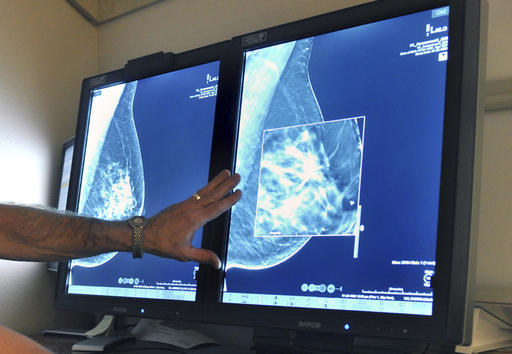

A new study questions the value of mammograms for breast cancer screening. It concludes that a woman is more likely to be diagnosed with a small tumor that is not destined to grow than she is to have a true problem spotted early.

Mammograms do catch some deadly cancers and save lives. But they also find many early cancers that are not destined to grow or spread and become a health threat. There is no good way to tell which ones will, so many women get treatments they don’t really need. It’s a twin problem: overdiagnosis and overtreatment.